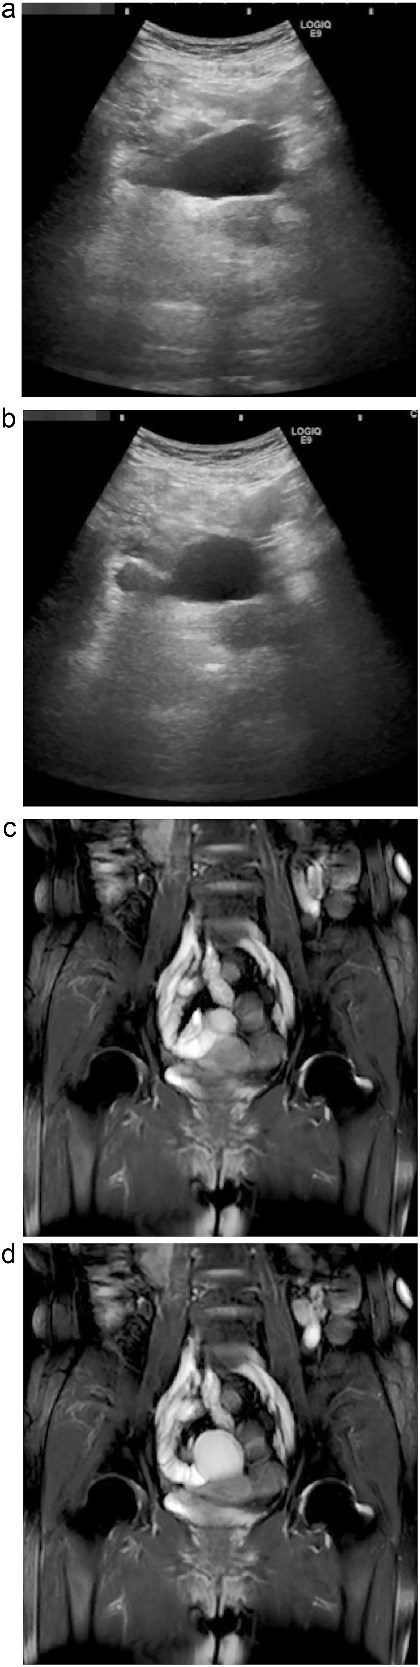

Subsequent abdominal ultrasonography revealed a well-defined cystic mass with a distinct layered wall. Notably, real-time observation demonstrated peristaltic movement of the lesion over several seconds, suggesting active smooth muscle within the wall (Fig. 1a and b; Supplementary Video 1). Magnetic resonance imaging (MRI) further characterized the lesion as a hyperintense structure on T2-weighted imaging, again demonstrating peristaltic activity on sequential dynamic sequences (Fig 1c and d; Supplementary Video 2). The cyst was closely attached to the ileum but showed no communication with the intestinal lumen.

Dynamic ultrasonography and MRI of the abdominal cystic lesion. (a, b) Abdominal ultrasonography revealed a 6-cm cystic lesion with a layered wall structure. Image (b) was taken 4 s after (a), showing deformation of the cyst wall, indicating peristaltic motion. (c, d) Coronal T2-weighted MRI demonstrated a high-intensity cystic lesion adjacent to the ileum. Image (d) was obtained 1.5 s after (c), also showing peristaltic movement of the cyst wall. These dynamic imaging features suggested a duplication cyst with smooth muscle activity.